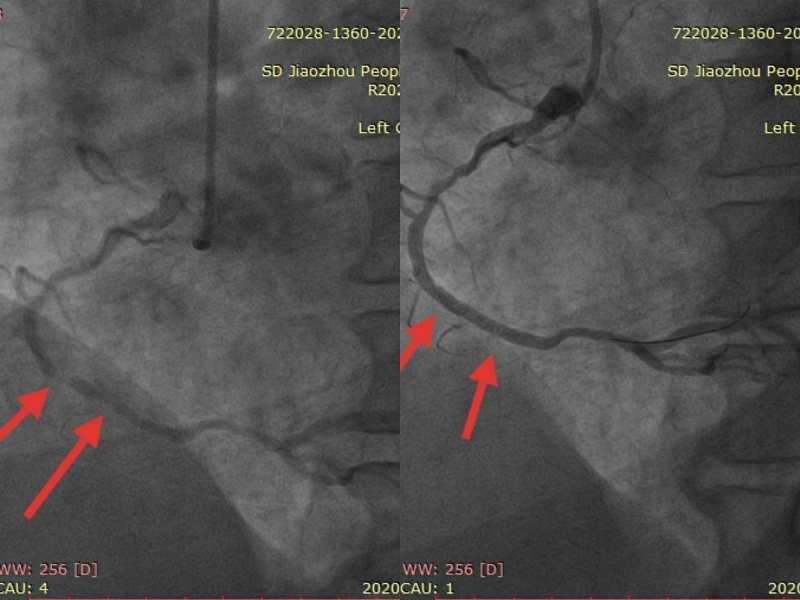

患者徐大爷夜间持续性胸痛急呼120,市人民医院院前急救出诊,通过车载心电图显示急性下壁ST段心肌梗死,出诊医师立即予以“心梗一包药”口服,并送达南院急诊科予以紧急救治,患者胸痛症状缓解,复查心电图ST段回落,收入急诊科病房。结合患者病情特点,经会诊后立即行冠脉造影术进一步检查血管情况,可见患者下壁中远段次全闭塞,予以支架植入,术后无不适症状,即将顺利康复出院。